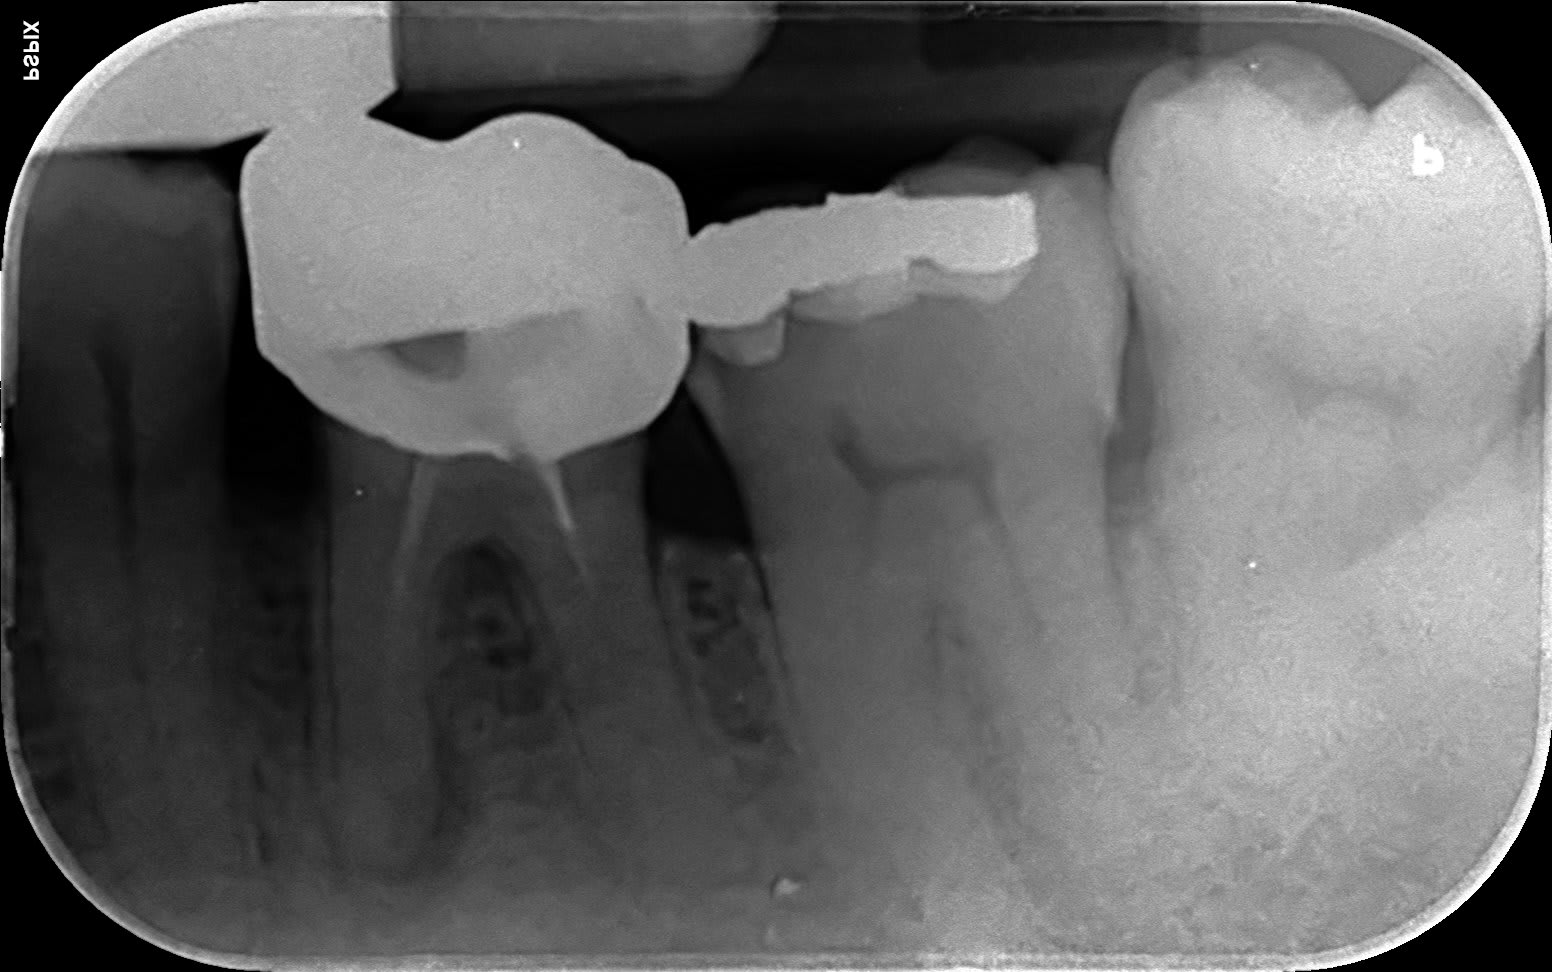

Regarde moi ça Vulpi , celui-ci je lui ai mis 7 implants qui sont en train de prendre au maxillaire, je lui fais un bridge à droite pour l’occlusion. Et à gauche il a une grosse boule semi molle qui est apparue sur la face interne de la joue. Il ne veut pas que je lui case une 36 sur implant ...

C’est quoi ça ? Juste une hypertrophie gingivale en regard des dents manquantes ? Tu découpes ça comme une tranche de jambon ... ?